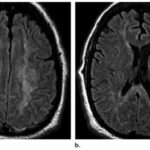

En el caso que se viene ilustrando, la RM mostró T2 difuso con hiperintensidades en el cuerpo calloso bilateral frontal y parietal, así como lesión difusa de la sustancia blanca del cerebelo. Se localizaron áreas de difusión restringida en los ganglios basales bilaterales, lo cual tenía relación con la pérdida neuronal mediada por estrés oxidativo (ver Imágenes 15 y 16). El tratamiento permitió la recuperación progresiva del habla y la orientación de la persona. (23)